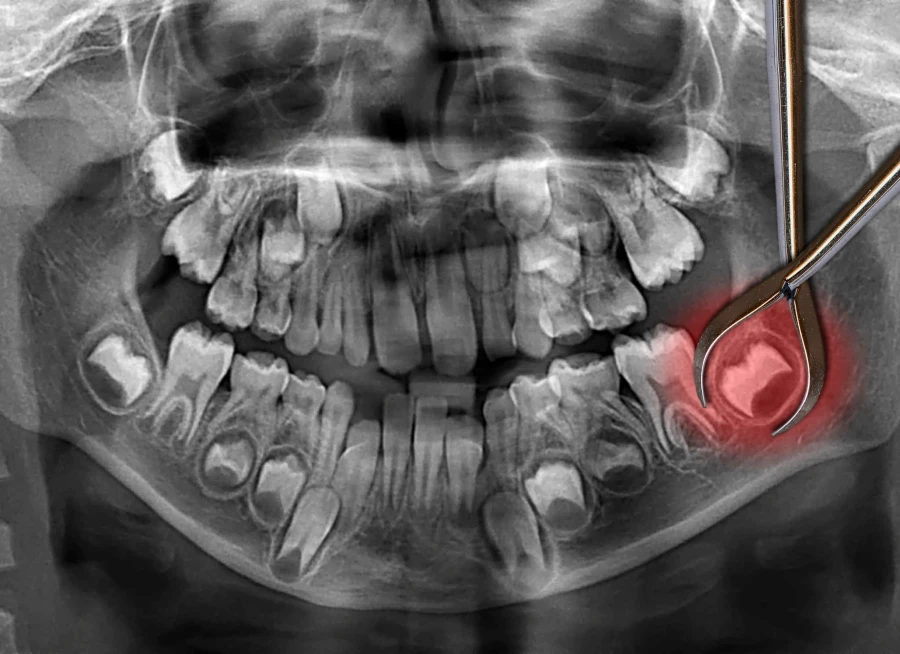

Consentement éclairé pour l’extraction de dents de sagesse

La F.A.Q de la dent de sagesse : avant l’intervention

Extraction de dents de sagesse : conseils avant et après l’intervention